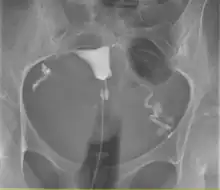

L'hystérosalpingographie est un examen de radiologie qui permet de visualiser l'utérus ainsi que son col et les trompes de Fallope.

On commence par introduire dans le vagin un spéculum. Ensuite on place sur le col de l'utérus une sonde ou des pinces selon la morphologie du col, afin d'assurer l'étanchéité entre l'utérus et le matériel d'injection. Ensuite on gonfle le ballonnet et on injecte dans l'utérus, puis dans les trompes, un produit de contraste, souvent à base d'iode, qui est opaque aux rayons X. On prend ensuite plusieurs clichés radiologiques au fur et à mesure de la diffusion du produit. On suit le parcours dans l'appareil génital du produit, lorsqu'il remplit puis désemplit l'utérus. Remarque : Cet examen ne permet pas l'exploration des ovaires. Cet examen nécessite un test Beta HCG négatif le jour de l'examen, réalisé dans les 48h avant ("test de grossesse par analyses de sang"), la prise d'antispasmodiques la veille au soir et les heures qui suivent l'examen, et éventuellement d'antibiotiques oraux et vaginaux la veille et les jours qui suivent l'examen.

Il y a d'abord un premier cliché sans l'ajout du produit de contraste qui permettra par la suite de visualiser l'appareil génital. On introduit ensuite le produit de contraste avec du matériel à usage unique. À l'aide d'une petite sonde positionnée dans le col utérin, un liquide à base d'iode est introduit dans l'utérus puis les trompes, il s'agit du produit de contraste, pour qu'il ne sorte pas immédiatement pas le col, on gonfle un ballonnet de manière que le produit remonte vers les trompes.

Des clichés sont pris en cours de remplissage de l'utérus et des trompes suivis d’un cliché tardif (20 minutes après la fin de l’examen).